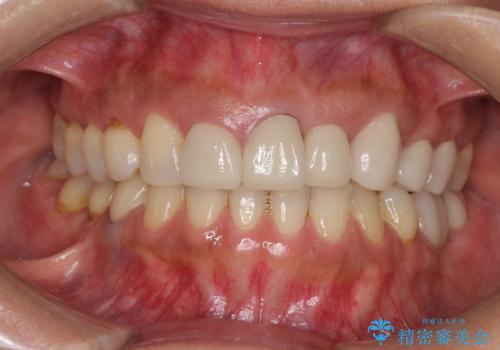

- 前歯の歯肉の高さが左右で異なっていることを気にして来院された患者様です。

歯肉レベルを調整するために歯周外科処置をおこない、その後にオールセラミッククラウンにて補綴することとしました。

歯肉の位置を整えるには歯周外科処置が必要であると説明した際には、なかなか踏み切ることができず、大変悩まれていました。

処置後の痛みはあまり気にならず、歯肉位置の左右差もほとんどなくなり、患者様には大変満足していただきました。